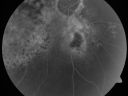

Pigmented Choroidal Mass Right Eye - Melanoma vs. Nevus vs. Unilateral Melanocytic Proliferation - 4 Month Follow-Up Images692 views71-year-old man his vision 4 month follow-up. Vision is 20/60 and patient sees flashing lights. Lesion has grown slightly in the superior half of the macula.     (0 votes)

PHOTOGRAPHS: Photos confirm clinical findings.

FLUORESCEIN ANGIOGRAPHY: The right eye shows hyperfluorescence corresponding to a window defect overlying the nevus. The choroidal vasculature can be easily seen throughout the area in a dependent fashion, suggestive of chronic subretinal fluid. There is also hyperfluorescence inferior to the optic nerve with hypofluorescence over the area of geographic atrophy. There is some stippled hyperfluorescence within the lesion in the late frame. The hyperfluorescence in general fades in the late frames. There is no evidence of any active leakage. The drusen over the surface of the nevus inferonasal to the optic nerve, which is overall dark, do stain in the late frames as well. The left eye is angiographically normal throughout the studies.